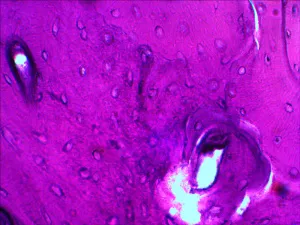

В наборе микропрепаратов:

- Дрозофила (личинка)

- Дрозофила (куколка)

- Дрозофила «норма»

- Животная клетка

- Растительная клетка

- Плесень

- Дробление яйцеклетки

- Митоз в корешке лука

- Поперечно-полосатые мышцы

- Сперматозоиды млекопитающего

- Нерв (поперечный срез)

- Рыхлая соединительная ткань

- Яйцеклетка млекопитающего

- Нервные клетки

- Гиалиновый хрящ

- Гладкие мышцы

- Костная ткань

- Кровь лягушки

- Кровь человека

- Однослойный эпителий

Примеры слайдов под микроскопом смотрите в галерее фотографий, а также в обзоре «Наборы готовых микропрепаратов Levenhuk» на сайте levenhuk.ru.